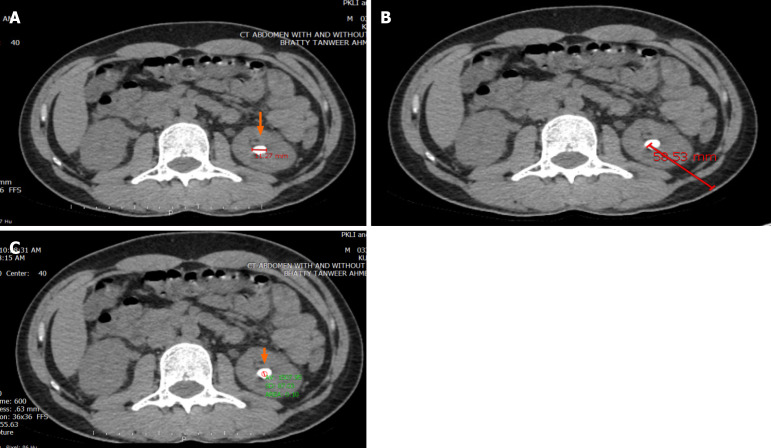

Methods: Charts review was utilized for collection of data variables. The patients were subjected to SWL, using an electromagnetic lithotripter. Mean stone density (MSD), stone heterogeneity index (SHI), and VCSD were calculated by generating regions of interest on computed tomography (CT) images. Role of these factors were determined by applying the relevant statistical tests for continuous and categorical variables and a P value of < 0.05 was gauged to be statistically significant.